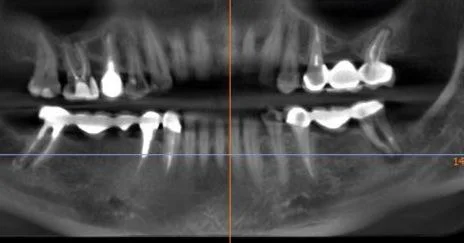

Видалення 4-х центральних різців, одномомента імплантація в ділянки 13, 21, 23, Кісткова пластика, тимчасові коронки.